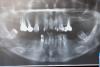

Pavel Y. Опубликовано 2 июня, 2013 Поделиться Опубликовано 2 июня, 2013 (изменено) Добрый вечер уважаемые коллеги. Вот наконец-то решил стать участником уважаемого форума. Как говориться, с пустыми руками неприлично... Работа двухлетней давности, многими методиками на том момент еще не владел. Поэтому критику ожидаю, но все же. Ведь это наше знакомство На нижней челюсти по данным КТ ширина гребня на нижней челюсти варьировала от 4-6 мм. Высота удовлетворительная. Принято решение провести имплантацию в позицию 34-36, 44-46. Удаление 37 зуба. Забор аутокости (стружка) с помощью "костного скребка" в третьем сегменте. Стабилизация мембраной Био Гайд Укладывается стружка:На тот момент я знал, что стружка под мембраной жить не сможет и, поэтому, я применил "сандвич" технику с Био осс (мелкий). Фиксация мембраны на пины:Многие скажут, что третья пина не нужна, но она так хорошо встала)))) Та же манипуляция проводится в четвертом сегменте: Ушивание раны. Через 2 недели снятие швов: Через 5 недель: До/После На сегодняшний день, пациентка отпротезирована временными реставрациями. С левой стороны потребовалась пластика мягких тканей, с правой второй этап проводился классически. Я понимаю, многим такой подход неприемлем и сейчас бы я применил уже другую тактику, но такая работа проведена и результат стабилен.Спасибо за внимание! Изменено 2 июня, 2013 пользователем Pavel Y. 1 Ссылка на комментарий